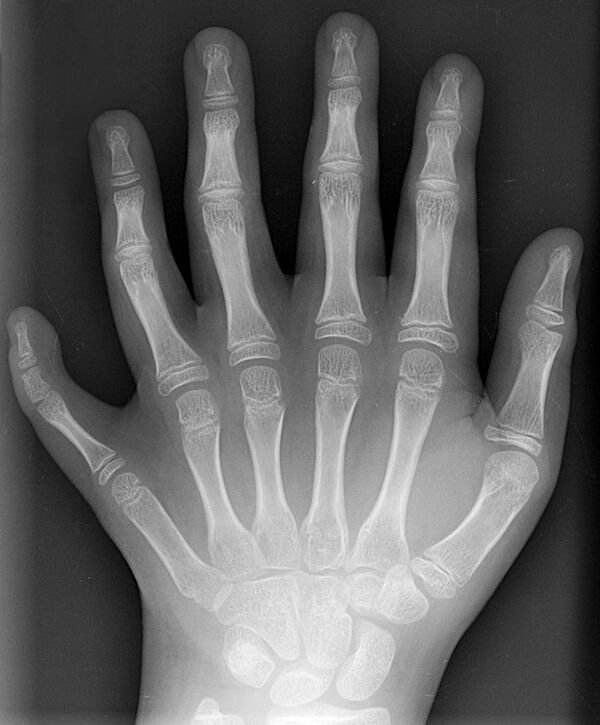

Полидактили́я (др.-греч. πολύς — много + δάκτυλος — палец, синоним — многопалость), также известная как гипердактилия — порок развития, характеризующейся бо́льшим, чем в норме, количеством пальцев на руках или ногах у человека, собак, котов и лошадей. Противоположным отклонением является олигодактилия.

У людей и животных она может проявляться как на одной, так и на обеих руках. Обычно дополнительный палец представляет собой небольшой кусочек мягкой ткани, которую можно удалить. Иногда это просто кость без суставов; очень редко лишний палец бывает полноценным. Дополнительный палец чаще всего образуется со стороны мизинца, реже на стороне большого пальца и очень редко между средними пальцами. Обычно лишний палец является аномальным разветвлением обычного пальца, редко возникает на запястье, как обычный палец.